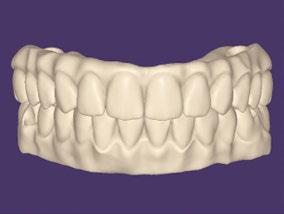

Figures 1A and 1B: 1A. Pre-extraction records. Patient presented with periodontal con cerns and extensive decay. 1B. Six LOCATOR® Implants (Zest Dental Solutions) were placed in strategic positions for a future fixed-prosthesis option

Figures 2A and 2B: 2A. A conventional prosthesis was fabricated with the intention to convert to a fixed prosthesis. 2B. LOCATOR FIXED housings were attached using intraoral pickup method and CHAIRSIDE Attachment Processing Material (Zest Dental Solutions)

Figures 3A and 3B: 3A. The prosthesis was trimmed and adjusted to eliminate the palate and flanges to convert into a fixed prosthesis. 3B. Processing inserts were replaced with LOCATOR FIXED (Zest Dental Solutions) inserts

Figures 4A and 4B: 4A. Before extractions and implants. 4B. After surgical procedures and prosthetic conversion into a fixed full-arch prosthesis